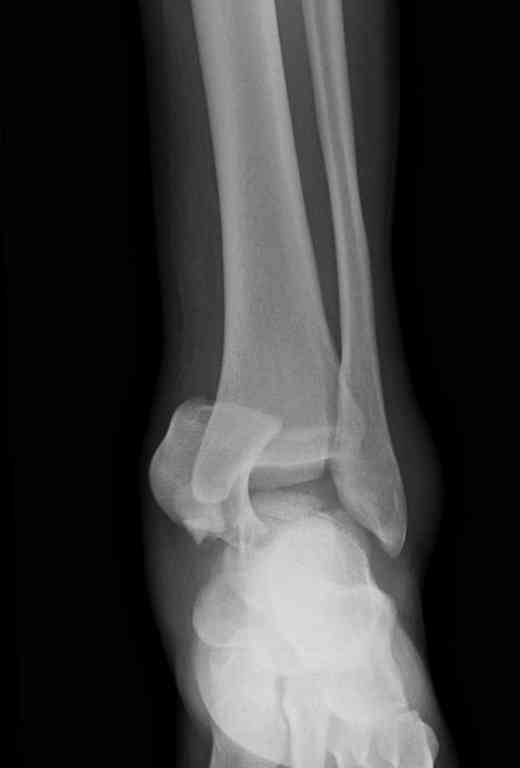

Вчера провели фиксацию.

Из-за многооскольчатости дистальной части малоберцовой, где невозможно было провести фиксацию шурупами, перелом зафиксирован подпирающей пластиной, которая должна служить дополнением отсутствующей дистальной части малоберцовой (lateral cortex substitute).

Для стабильности два шурупа на синдесмоз.

Медиальную рану с приближенными краями продолжаем вакуумировать (KCI). Наружный фиксатор оставлен на пару недель, надеюсь, небольшая рана будет гранулировать и закроется без кожной пластики. Фиксация медиальной ложыжки не планируется.